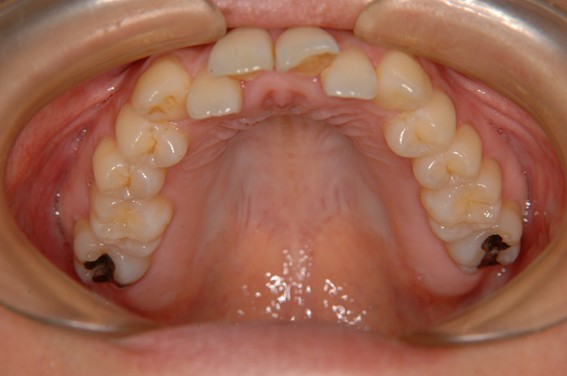

| 主訴 | 前歯が逆に噛んでいる。 |

| 治療内容 | 表側ワイヤー矯正、ジルコニア補綴を行いました。 |

| 治療費 | ワイヤー矯正660,000円(税込) ジルコニア176,000円(88,000円×2歯)(税込) |

| 治療期間 | 30ヶ月 |

| 治療回数 | 30回 |

| 想定されたリスク | 歯根吸収、歯髄壊死、歯髄充血、歯肉退縮のリスクがありました。 |

骨格性Ⅲ級・前歯部反対咬合の症例でした。反対咬合のまま治療していた前歯のサイズ不調和を、表側ワイヤー矯正とプロビジョナルクラウンで調整。正中を整え、犬歯・臼歯ともⅠ級、適切なオーバージェット(上下前歯の前後的な距離)・オーバーバイト(上下前歯の垂直的な重なり)に仕上げました。